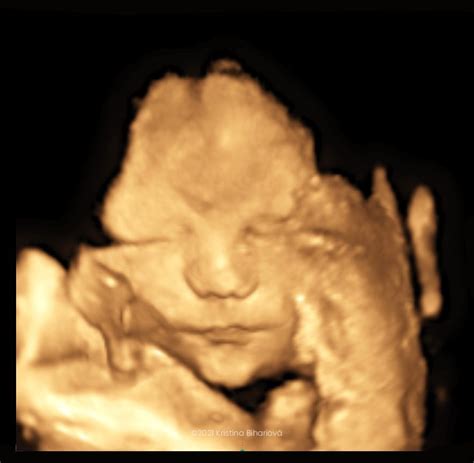

Klasický 2D ultrazvuk, ktorý sa bežne vykonáva v tehotenských poradniach, poskytuje dvojrozmerný obraz plodu. 3D ultrazvuk je pokročilejšia metóda, ktorá zobrazuje plod trojrozmerne. Hoci 3D ultrazvuk poskytuje plastický, no statický obraz, jeho hlavným cieľom je často estetické potešenie rodičov. V rámci prenatálnej diagnostiky je 3D ultrazvuk doplnkom k 2D ultrazvuku, no môže poskytnúť detailnejší pohľad na niektoré časti plodu, ako je chrbtica, kostra či srdce. Pri 4D ultrazvuku sa k trojrozmernému obrazu pridáva aj rozmer času, čo umožňuje vidieť pohyby bábätka v reálnom čase.

Zatiaľ čo 2D ultrazvuk poskytuje lekársky smerodatné dvojrozmerné zobrazenie, 3D ultrazvuk zobrazuje plod v trojrozmernom, statickom obraze, slúžiaci skôr na estetické účely. 4D ultrazvuk ide ešte o krok ďalej a umožňuje vidieť pohyby bábätka v reálnom čase, čím vytvára dynamické video.

Pri 3D a 4D ultrazvukoch je dôležitá spolupráca bábätka a dostatočné množstvo plodovej vody pre čo najlepší výsledok. Ideálny čas na tieto vyšetrenia je po 18. týždni tehotenstva, kedy je bábätko dostatočne vyvinuté.

3D ultrazvuk je skvelou možnosťou, ako získať jedinečnú spomienku na obdobie tehotenstva. Umožňuje rodičom vidieť tvárové rysy svojho dieťatka, získať realistickú predstavu o tom, ako bude vyzerať po pôrode a potvrdiť pohlavie. V prípade, že dieťatko nie je v čase vyšetrenia správne otočené, ambulancia zvyčajne ponúka náhradný termín bez doplatku.

Aj keď sa 3D ultrazvuk vykonáva najmä z komerčných dôvodov, môže byť užitočný aj pri diagnostike niektorých vrodených chýb, najmä tých viditeľných na tvári či končatinách.